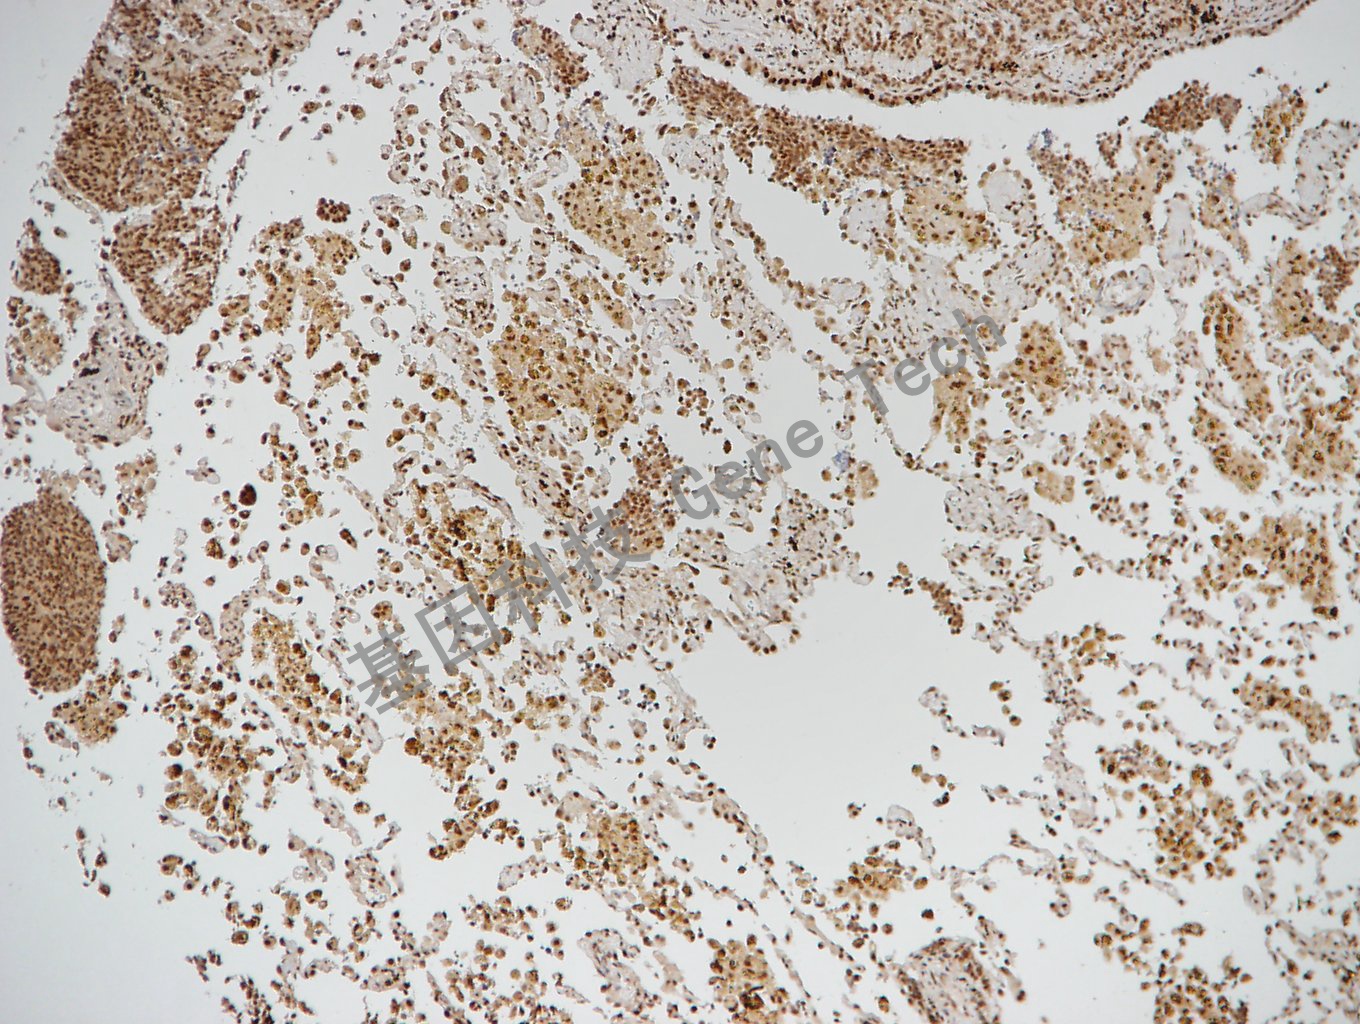

前列腺癌石蜡切片,用 ERCC1(GT2155)染,细胞核阳性,DAB 显色。

阑尾石蜡切片,用 ERCC1(GT2155)染,细胞核阳性,DAB 显色。